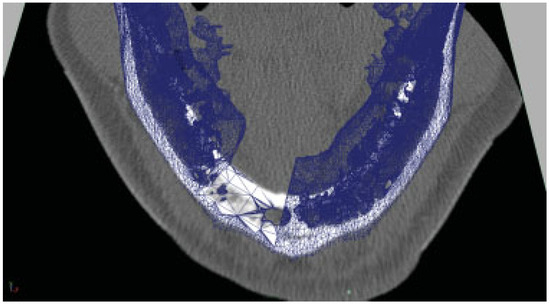

An isosurface reconstruction was carried out in Osirix© 3.2 (Wavefront Technology, Edmonton, Alberta, Canada) using a Hounsfield level of 500. The reconstruction was exported from Osirix© as a geometry definition file, *.obj. The polygon jaw was then transferred to Autodesk Maya 2009 (Autodesk®, San Rafael, CA). The DICOM images stack was exported to *.tiff (Adobe System Inc., San Jose, CA) and imported as an image sequence into Maya® 2009 (Autodesk®, San Rafael, CA). The polygon jaw was then aligned with the image sequence and virtual resection was carried out (Figure 1), and a saw guide was designed (Figure 2A,B). The virtual saw guide was compared to the image sequence for treatment plan accuracy. In the remaining cases, the treatment plan was carried out in Surgicase© (Materialise©, Leuven, Belgium). The *.stl-file (3D System Corp, Rock Hill, SC) from the reconstructed mandible/fibula was transferred to a Macintosh© Mac Book Pro©, 2.16 MHz, Duel Core Intel® processor with two Gigabyte RAM, (Apple© Corp., Cupertino, CA) and imported into 3-D animation program Maya 2009. The specification of a Compact UniLOCK® 2.4 large plate (Synthes®, Switzerland) was used. The geometry was scaled down by 25%. The polygon mesh was skinned onto a skeleton, according to Dérand and Hirsch [5]. Plates were constructed with individualized screw holes (Figure 3) and exported as a geometry definition file, *.obj. The titanium mesh was constructed by mirroring the contralateral side and shaped with Fracture-FX (plug-in, Maya® 2009). All data were transferred over Internet to the Department of Engineering and Sustainable Development (Mid Sweden University, Östersund, Sweden) for additive manufacturing of the devices.

The saw guide was used in the operating theater, checked against the mandible (Figure 4), and then used to perform the planned osteotomies.

Figure 2. (A) A saw guide was designed. (B) The EBM-produced titanium saw guide shown on a plastic model of the mandible.

Figure 3. The saw guide was checked against the patient mandible.